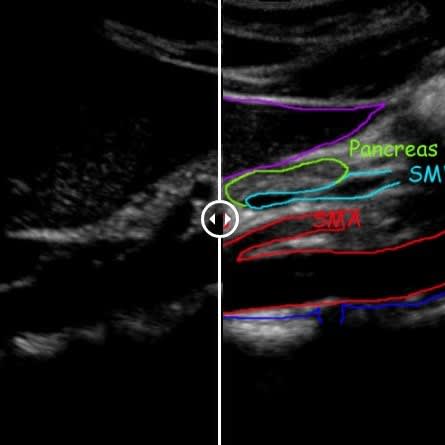

Vascular Services

Allow our dedicated team to put you at ease, while we boast about having top of the range equipment and overqualified staff. Outstanding patient care comes as standard here at NumiScan Basingstoke.